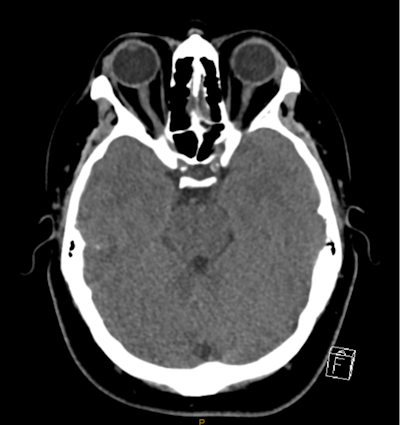

In this example of an incidental finding not being communicated to the patient's GP, a patient in their 30s presented to the emergency department with sudden onset of syncope and associated head injury. After a brain and cervical spine CT, the radiologist documented incidental moderate bilateral internal carotid artery calcification. All figures courtesy of Dr. Chester Yeung et al and presented at RANZCR's 2024 ASM.